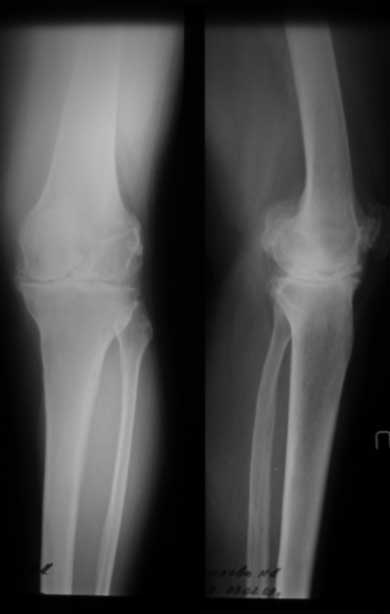

Уважаемые коллеги, как боретесь с ригидным коленом в положении разгибания при эндопротезировании? Пациентка 67 лет, ригидное колено в положении полного разгибания с качательными движениями до 5 град. Прооперировали внутренним доступом с отсечением бугристости. Сгибание до рефиксации бугристости - до острого угла, после максимум с/р 20-25/0/0. Выполнили миолиз доступных отделов 4-х главой мышцы бедра из доступа без особого результата. Основная проблема была в разгибательном аппарате, как с этим боретесь? До эндопротезировыания или после - полноценные операции на разгибательном аппарате как при контрактурах. P.S. снимки выложу чуть позже (не могу добиться нормальных проекций), грубых косяков пока не заметил (увеличенный offset и т.д.) С уважением Максим Агалаков, Е-бург

причина- длительно текущий коксартроз, протезировать надо было на момент постановки в очередь, прошло 5 лет.

Разгибетельная контрактура нехарактерна для первичного гонартроза. О фактах травмы, иммобилизации, спастике разгибательного аппарата вы ничего не сказали.